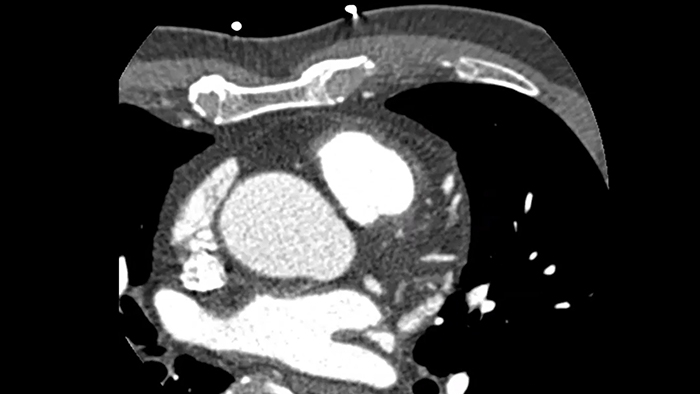

Overcome cardiac imaging challenges

Motion-free cardiac imaging improves image quality at high heart rates